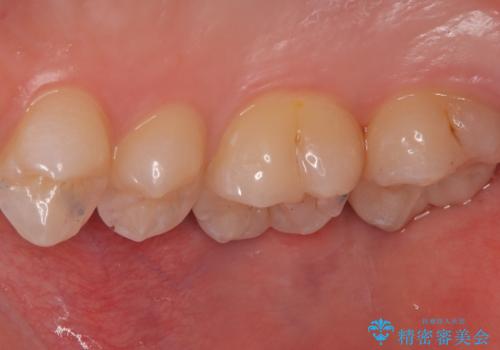

左上一番奥の歯の頬側に実質欠損を伴う虫歯が存在したため、セラミックインレーでの治療となりました。

上顎左側第二大臼歯頬側面から遠心面、咬合面にもう蝕が波及していたためアンレー形態となりました。

清掃しずらい箇所ではあるため、汚れが付きづらい適合性のよいセラミック素材を選択しました。

セラミックアンレーセット時、ラバーダム防湿を行っています。